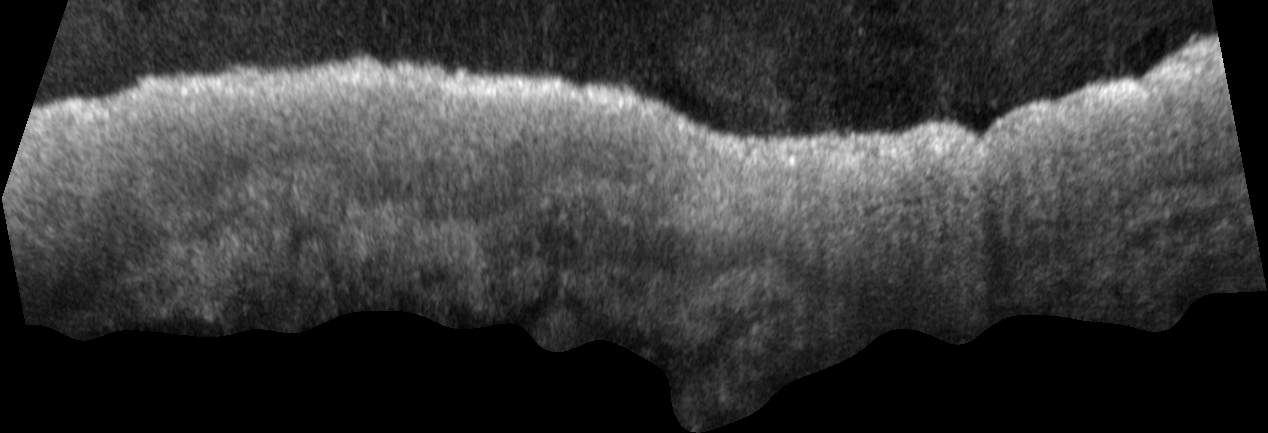

Refer to caption

Figure 1: Tissue segmentation of OCT images utilizing FoundationShift and off-the-shelf segmentation models. a) Off-the-shelf segmentation foundation models perform poorly when segmenting OCT images. b) By performing domain transfer first, we are able to significantly improve segmentation accuracy. c,d) Segmentation examples of off-the-shelf algorithms compared to our approach (Domain Transfer + MedSAM). Ground truth expert epidermis segmentation is highlighted in green contour. Algorithm segmentation is visualized in blue. e) Dice similarity coefficient quantification for each algorithm. The center line within the colored box represents the median value, with the bottom and top bounds of the box delineating the 25th and 75th percentiles, respectively, whiskers represent minimum and maximum scores over the 95 sections. Domain transfer followed by MedSAM outperforms all off-the-shelf algorithms tested (p<21015𝑝2superscript1015\leavevmode\nobreak\ p<2\cdot 10^{-15}). f) Domain transfer + MedSAM perform 3D segmentation of skin sample containing a Basal Cell Carcinoma nodule (orange). Epidermis segmentation visualized in blue. g,h) 2D cross-sectional views from within the volume, which can be chosen to slice across any plane. Scale bars in c,f,h) are 200 µmtimes200micrometer200\text{\,}\mathrm{\SIUnitSymbolMicro m}.

We first demonstrate FoundationShift utilizing OCT images. We collected a 17 skin samples yielding a total of 95 paired OCT and H&E skin images from the arm and face regions. We utilized OCT2Hist [14], to convert OCT images to H&E-like images prior to off-the-shelf segmentation models. A few examples from the dataset are shown in Figure S1.

We compared the accuracy of three off-the-shelf segmentation foundation models. Segment Anything (SAM [23]) is a generic segmentation model that was trained on 11M generic images and is considered a task-agnostic model. In addition, MedSAM [24] was tuned by Ma et al. utilizing 1.5M medical images, with 9.3K pathology images and 800 OCT images. Finally, SAM-Med2D [25] was tuned utilizing 330K pathology images and no OCT images. We hypothesized that FoundationShift would improve segmentation model accuracy, and that the improvement would correlate with number of pathology images in segmentation model training set. As expected, all models experience Dice score increase when utilizing domain transfer (Figure S4), and Domain transfer + SAM-Med2D significantly outperforms all tested algorithms (Figure 1e).

Notably, as OCT is a 3D imaging modality, FoundationShift offers a way to extend CPath from 2D sections to a 3D volume. In Figure 1f, we demonstrate creating a 3D contour of segmented epidermis, and a Basal Cell Carcinoma (BCC) nodule.